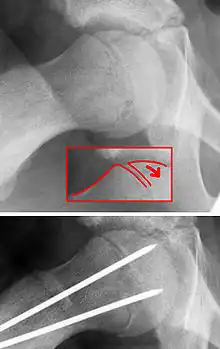

| X-ray showing a slipped capital femoral epiphysis, before and after surgical fixation. | |

The diagnosis requires x-rays of the pelvis, with anteriorposterior (AP) and frog-leg lateral views.[11] The appearance of the head of the femur in relation to the shaft likens that of a "melting ice cream cone", visible with Klein's line. The severity of the disease can be measured using the Southwick angle.

The disease can be treated with external in-situ pinning or open reduction and pinning. Consultation with an orthopaedic surgeon is necessary to repair this problem. Pinning the unaffected side prophylactically is not recommended for most patients, but may be appropriate if a second SCFE is very likely.[11]

Once SCFE is suspected, the patient should be non-weight bearing and remain on strict bed rest. In severe cases, after enough rest the patient may require physical therapy to regain strength and movement back to the leg. A SCFE is an orthopaedic emergency, as further slippage may result in occlusion of the blood supply and avascular necrosis (risk of 25 percent). Almost all cases require surgery, which usually involves the placement of one or two pins into the femoral head to prevent further slippage.[12] The recommended screw placement is in the center of the epiphysis and perpendicular to the physis.[13] Chances of a slippage occurring in the other hip are 20 percent within 18 months of diagnosis of the first slippage and consequently the opposite unaffected femur may also require pinning.

The risk of reducing this fracture includes the disruption of the blood supply to the bone. It has been shown in the past that attempts to correct the slippage by moving the head back into its correct position can cause the bone to die. Therefore the head of the femur is usually pinned 'as is'. A small incision is made in the outer side of the upper thigh and metal pins are placed through the femoral neck and into the head of the femur. A dressing covers the wound.